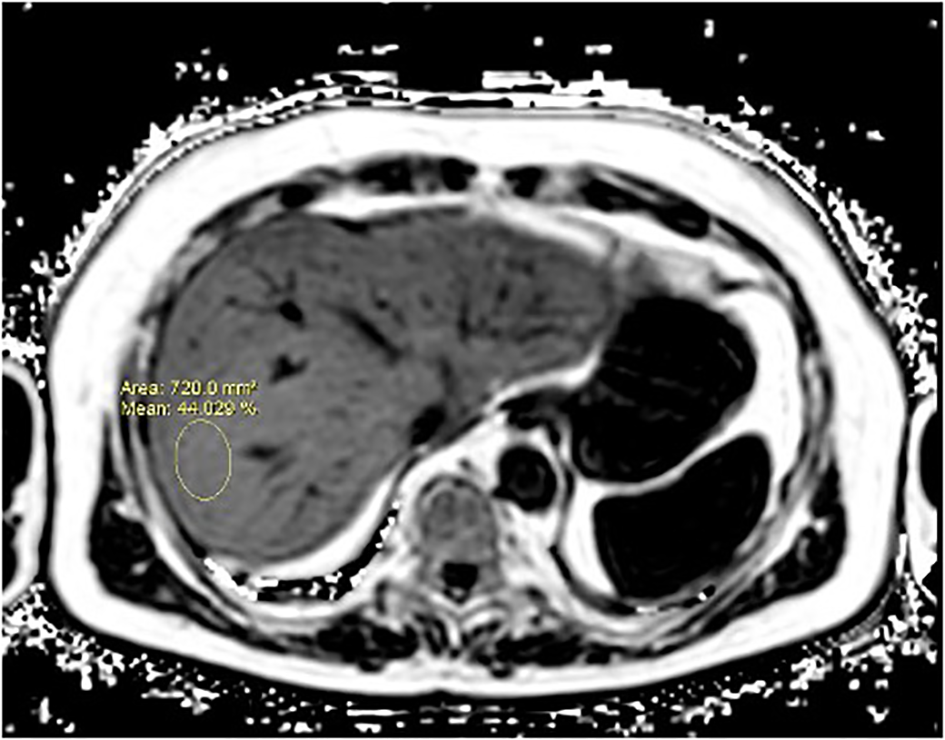

The volunteers subsequently underwent MRI: 28 subjects (23.9%) had no steatosis (steatosis percentage <5%), 64 (54.7%) had mild steatosis (steatosis percentage 6%–33%), and 25 (21.4%) had moderate steatosis (steatosis percentage 34%–66%). No subjects with severe steatosis (>66%) were identified (Table 1). GE T1-weighted in-phase images show loss of hepatic signal on opposed phase images, demonstrating the presence of steatosis (Figures 2A, B). However, a quantification of fat fraction is not possible. On the other hand, both spectroscopy and PDFF sequence allow a reliable evaluation of the liver fat fraction. The PDFF sequence allows to evaluate the whole liver (Figures 3, 4).

Figure 4

A case of NAFLD evaluated with PDFF. PDFF offers a precise, non-invasive quantification of liver fat content, covering the entire organ and providing consistent, reproducible results. It also correlates well with histopathological findings, making it a reliable alternative to biopsy for comprehensive liver fat evaluation.